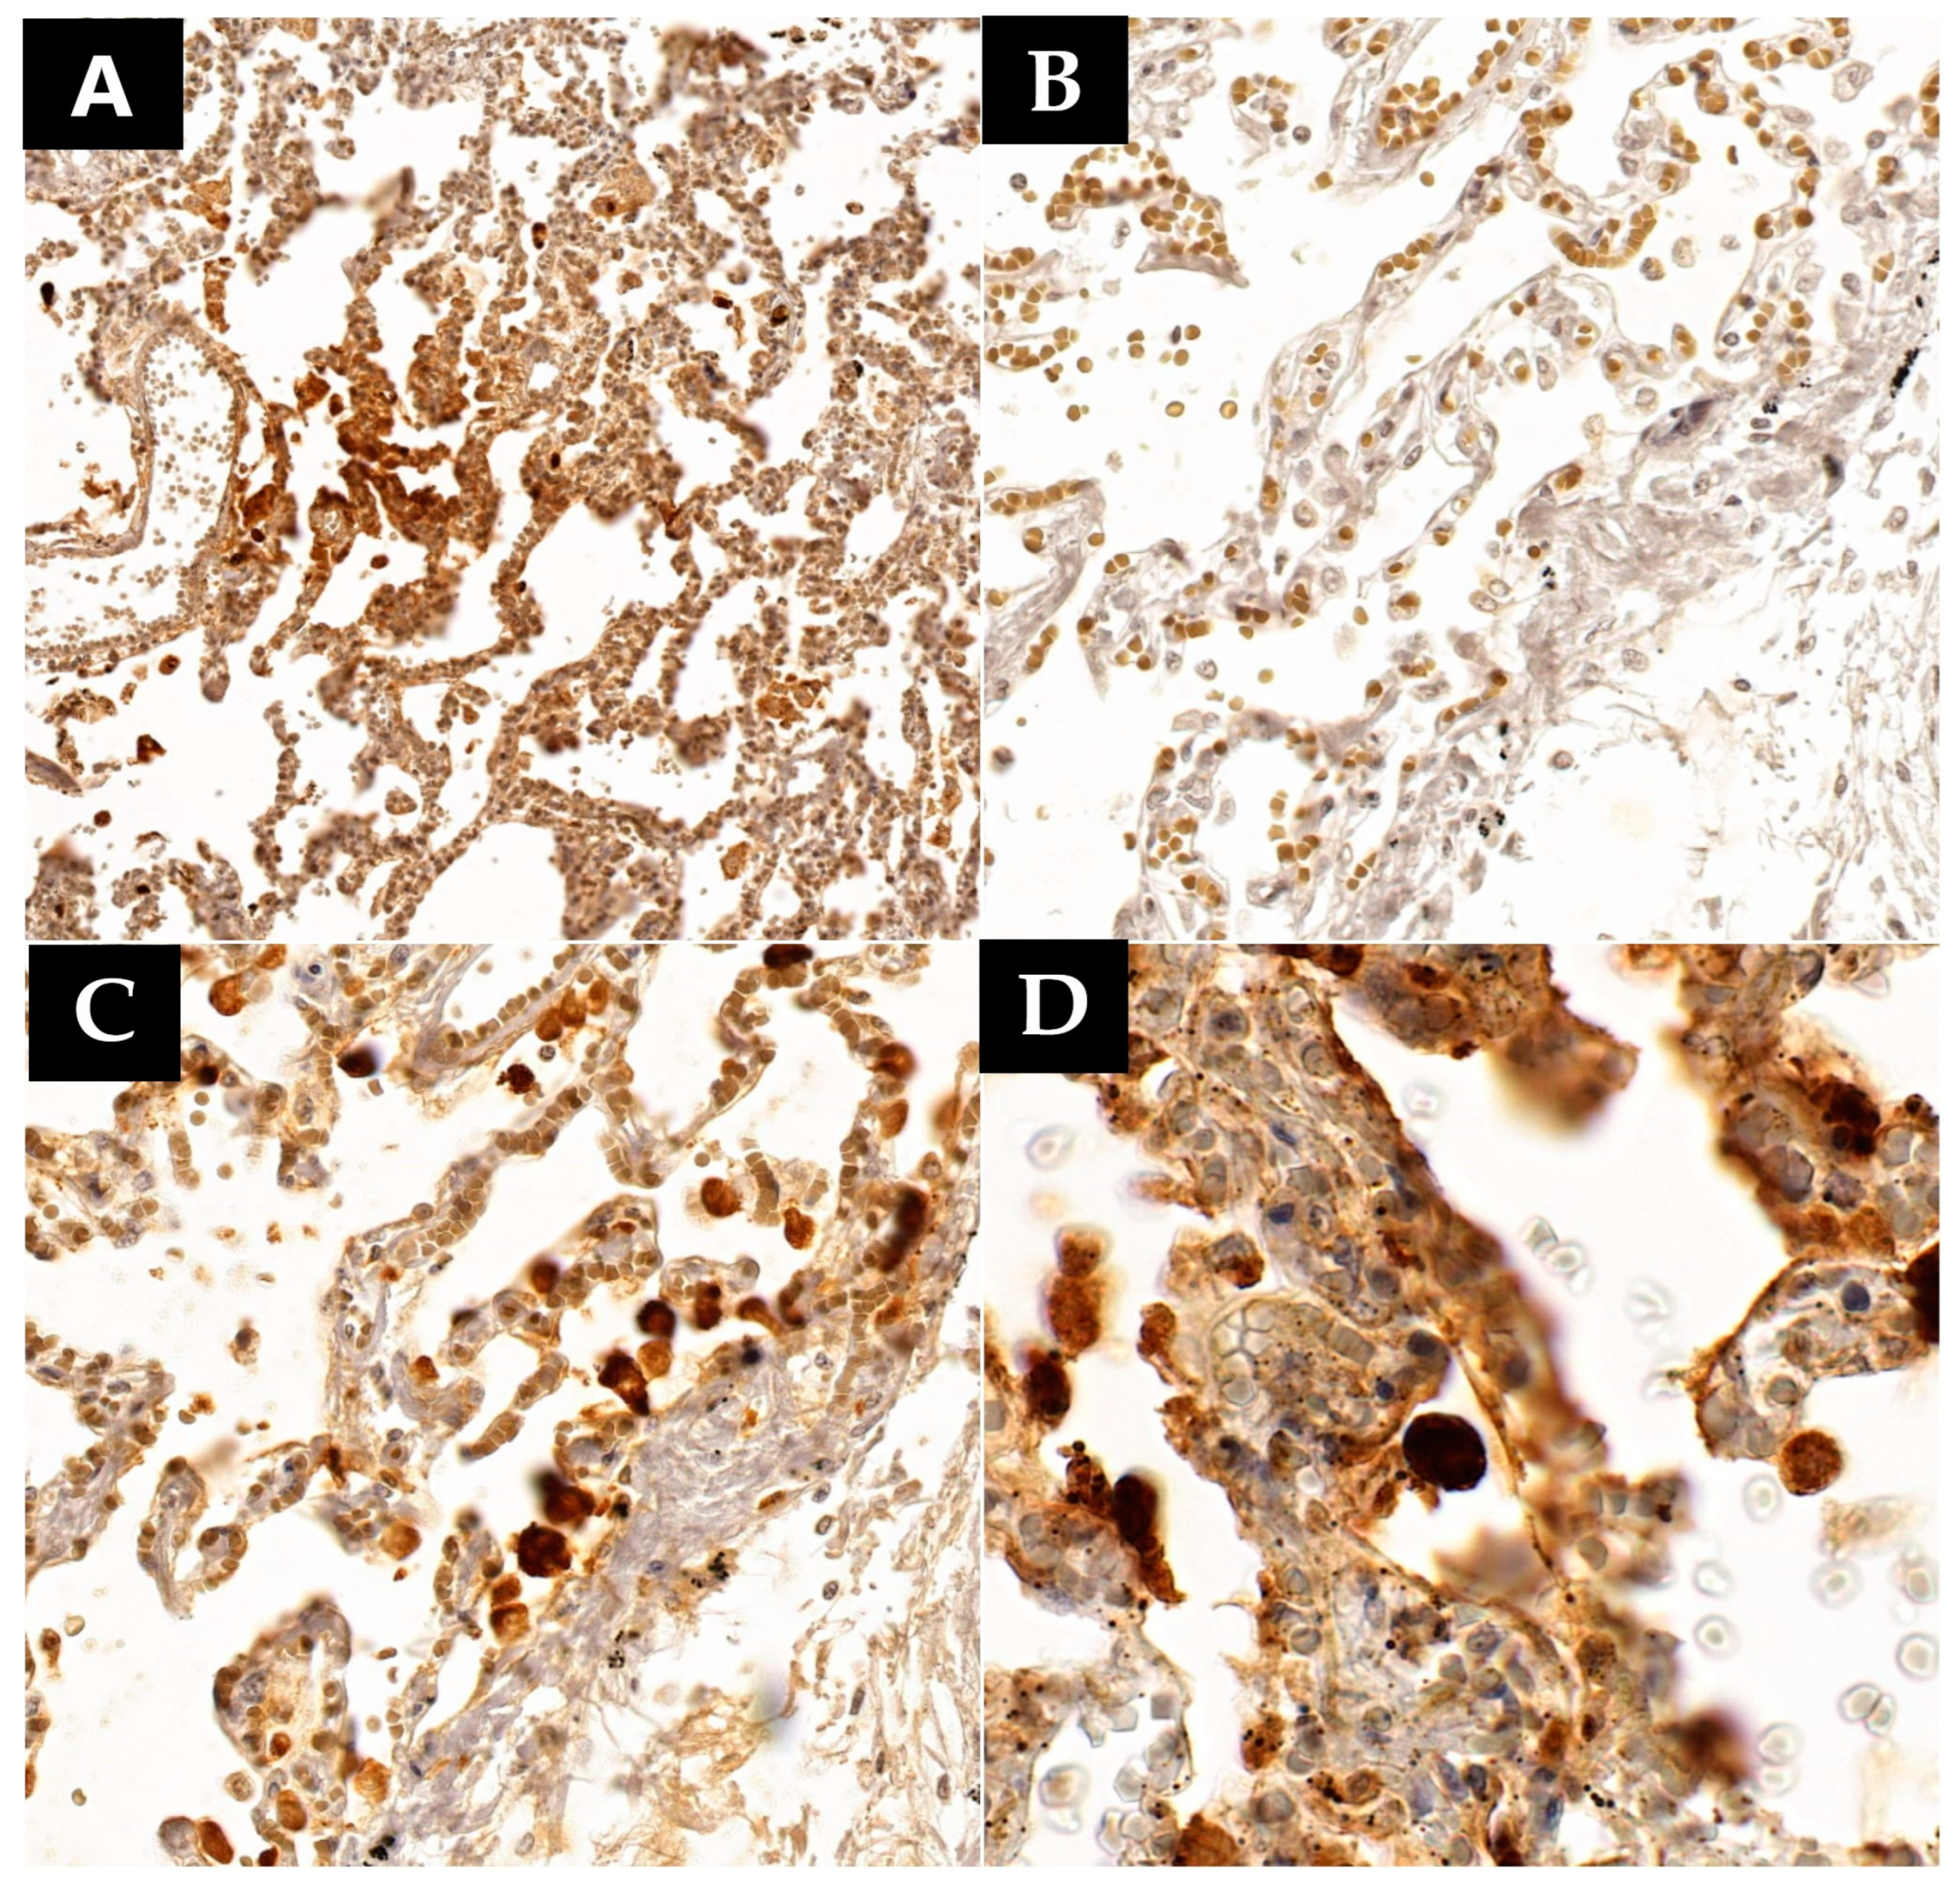

Immunohistochemistry also revealed a high positivity count in lung tissue, translated by the presence of the nucleocapsid protein in 12 out of 15 cases (

Table 3), mostly found at the level of the type II pneumocytes and the multinucleated giant-cell like aggregates (all 12 cases), in the alveolar macrophages (9 cases) or fibroblasts (6 cases), and in the hyaline membranes in the cases where this membrane formation was observed (5 cases) (

Figure 4). Regarding the pneumocytes, seven cases exhibited extensive positivity, surpassing one pneumocyte per microscopic field at 400× magnification, while in five cases, the positivity was less extensive, below one infected cell per microscopic field at 400× magnification (

Figure 4). Since the detection of the nucleocapsid by the specific antibody induces a cell-staining reaction, and the staining intensity is directly proportional to the number of proteins in the cell, a more intense staining suggests a higher nucleocapsid presence. Each evaluated specimen was quantified based on the staining intensity of the infected cells. Of the seven cases with extensive positivity (>1 cell/400× field) for the anti-nucleocapsid antibody at the pneumocytic level, all cases exhibited intense positivity in each infected cell. All these patients succumbed directly to acute respiratory distress syndrome (ARDS) secondary to severe viral pneumonia. Among them, four had a confirmed infection onset between 1 and 7 days before death, one patient passed away 15 days after infection confirmation, and the last two patients died after 21 or 28 days post-SARS-CoV-2 infection confirmation. In the group positive for less than one cell/400× microscopic field (five cases), a total of three cases exhibited intense positivity to the same antibody. The first of these three patients died one day after infection confirmation from ARDS secondary to viral pneumonia. The second patient succumbed 23 days after infection onset, also from severe pulmonary lesions associated with viral pneumonia. The last patient from this group died after 15 days of infection confirmation, with the cause of death being bacterial bronchopneumonia. The last two cases showed only weak focal positivity to the specific antibody. One of them died after 7 days of infection onset due to a massive pleural effusion. This patient had very few lesions consistent with viral pneumonia, such as a high number of macrophages within the alveolar spaces and type II pneumocyte hyperplasia, but also focal pulmonary fibrosis. Instead, this patient presented a pulmonary neoplasm triggering a massive pleural effusion in association with mild viral pneumonia. The second patient died 68 days after infection onset from a massive pulmonary edema, most likely secondary to acute cardiac insufficiency. The patient was hospitalized for almost the entire time, surviving severe viral pneumonia with multiple bacterial superinfections. The last three patients from our study group were all negative for the SARS-CoV-2 nucleocapsid, and death was triggered either by bacterial superinfection or spontaneous retroperitoneal hemorrhage secondary to anticoagulant therapy. The time span between infection confirmation and death in these last three patients ranged from 1 to 25 days. Upon comprehensive analysis of these results, a pattern emerges. The nucleocapsid is extensively present in large quantities in patients who develop severe diffuse alveolar damage in the first three weeks of infection. After three weeks, the nucleocapsid is still present but more focally and in lesser quantities. However, it can still be detected in small quantities even after 68 days after infection onset, even in patients who no longer exhibit lesions consistent with acute viral pneumonia.

Following immunohistochemical analysis using the anti-SARS-CoV-2 nucleocapsid antibody, detection was observed in 12 out of 15 cases. The most intense positivity was noted in pneumocytes, with detection being possible in type II pneumocytes, most of which exhibited viral cytopathic effects or the formation of syncytial giant cells in all 12 cases. Nucleocapsid was simultaneously present in macrophages in nine patients, in fibroblasts in six patients, and in hyaline membranes where they were present in five patients. Viral nucleocapsid was present in all cases where pneumocytes with viral cytopathic effects were observed and in all cases presenting pneumocytic syncytial giant cells. Although the detection of the nucleocapsid through immunohistochemistry was weak and focal, it could still be achieved even after 68 days from the onset of infection. Similar results regarding nucleocapsid detection in the lung and its persistence over an extended period have been reported in the specialized literature [